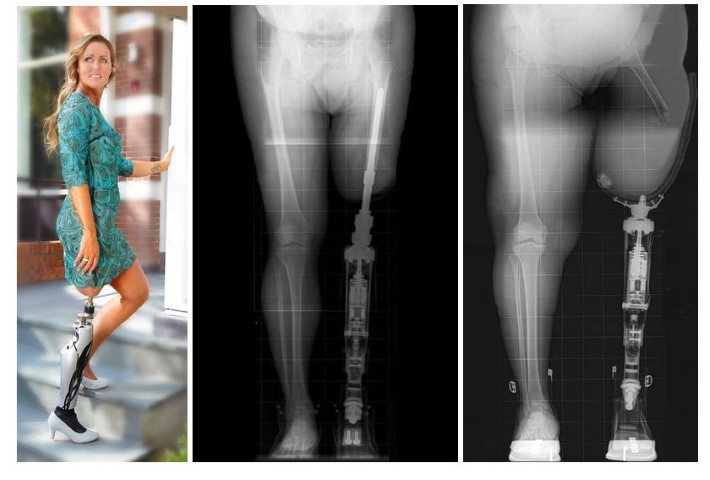

[et_pb_section bb_built=”1″][et_pb_row][et_pb_column type=”4_4″][et_pb_text _builder_version=”3.0.63″ background_layout=”light” text_orientation=”left” border_style=”solid”] Amper enkele maanden nadat Hulotech met de MJF printer van HP aan de…

Xilloc Medical neemt OTN over. Dit bedrijf heeft de orthopedische Click Safety Adapters ontwikkeld, dat wereldwijd wordt verkocht. Daarmee wordt…